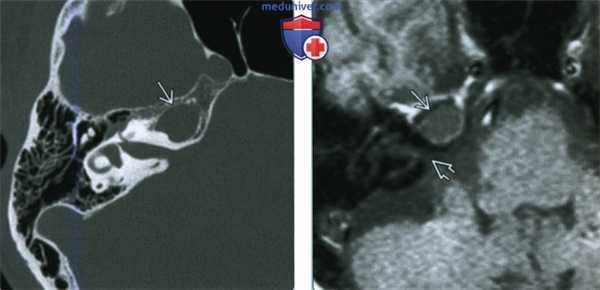

(Слева) При аксиальной КТ в костном окне определяется экспансивное поражение вершины пирамиды (ВП) справа с отсутствием ячеек, в норме заполненных газом, и трабекул. Дифференциально-диагноаический ряд: врожденная холестеатома, холестериновая гранулема, мукоцеле.

(Справа) При аксиальной МРТ Т1 ВИ у этого же пациента определяется распространенное мукоцеле ВП с интенсивноаью сигнала минимально более высокой, чем у ЦСЖ. Обратите внимание на гипоинтенсивный сигнал (ЦСЖ) во внутреннем слуховом канале сразу же за мукоцеле. Низкоинтенсивный сигнал на Т1 ВИ исключает холестериновую гранулему.

(Слева) При аксиальной МРТ Т2 ВИ определяется равномерно гиперинтенсивный сигнал в мукоцеле ВП. На ДВИ (не показано) не обнаружено ограничения диффузии. Экспансивное поражение ВП с гипо- (Т1) и гипер- (Т2) интенсивным сигналом и без ограничения диффузии крайне подозрительно на мукоцеле.

(Справа) При аксиальной МРТ Т2 у другого пациента определяется гиперинтенсивный сигнал (Т2) в экспансивном мукоцеле ВП. Сигнал Т1 гипоинтенсивный (не холестериновая гранулема), ограничение диффузии отсутствует (не врожденная холестеатома).